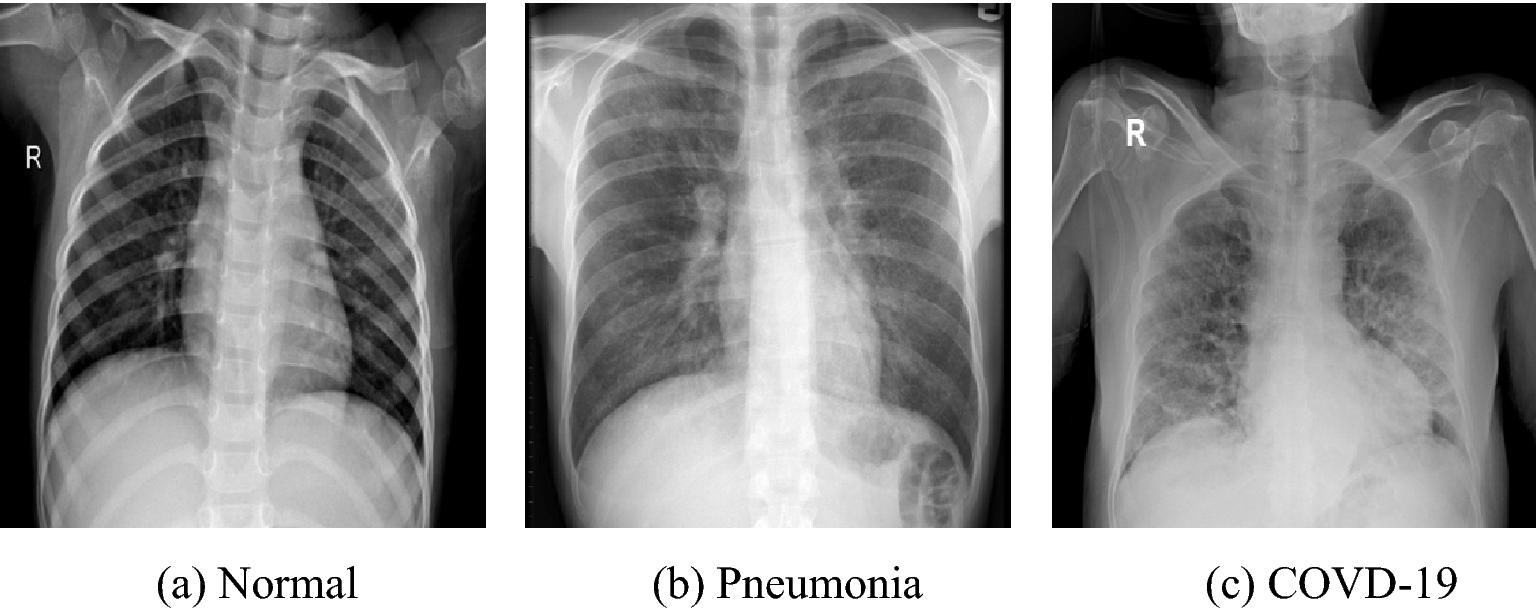

Detection of COVID-19 in X-Ray images

• Built a binary classification model using chest X-Ray images and VGG-16 convolutional neural network architecture pre-trained on ImageNet.

• New fully-connected layer was added to the pre-trained network to classify images as either normal or COVID-affected.

• Model was trained and achieved an accuracy of 93%.

In recent years, deep learning has shown promising results in medical image analysis, including detecting COVID-19 from chest X-rays. One popular approach is to use pre-trained convolutional neural network (CNN) models, such as VGG-16, ResNet, or DenseNet, and fine-tune them on COVID-19 chest X-ray datasets. The fine-tuning process involves removing the original classification layer and adding a new one to adapt the model to the specific COVID-19 detection task.

Besides using pre-trained models, researchers have also developed specialized architectures for COVID-19 detection. For example, COVID-Net is a CNN model specifically designed for COVID-19 detection from chest X-rays. COVID-Net uses a series of convolutional and pooling layers followed by several fully-connected layers to classify chest X-rays as normal, pneumonia, or COVID-19.

The goal of the project is to develop a machine learning model that can accurately and quickly detect COVID-19 infection from chest X-ray images. By achieving an accuracy of 93%, the model shows promise as a potential tool for COVID-19 screening and diagnosis.